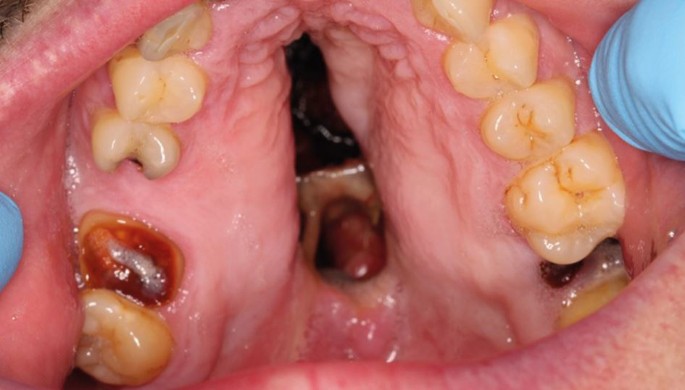

On examination, there was a loss of the nasal columella and saddle nose deformity. Intra-orally, there was complete erosion of the hard and soft palate and destruction of the nasal septum, with superimposed overgrowth of tissue and suppuration extending from the anterior hard palate posteriorly toward the oropharynx. The defect was surrounded with florid angiomatous tissue and bordered with crusted necrotic tissue (Fig. 5, Fig. 6). All remaining maxillary teeth were mobile (Fig. 7).

CIMDL with extensive oral and nasopharyngeal destruction